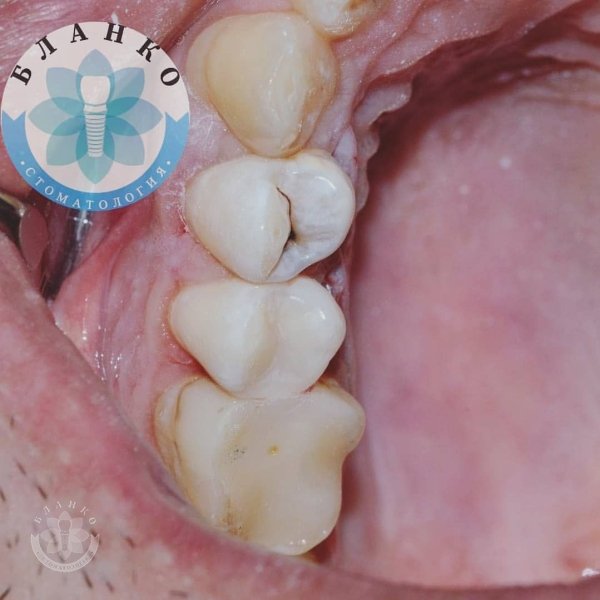

Глибока руйнація😳👿

Чим глибше під ясна зруйнований зуб — тим складніше він піддається адекватному відновленню☝

У даному клінічному випадку два зуби відновлено культевими вкладками, виготовлено коронки з оксиду цирконію, третій зуб відновлено за допомогою прямої фотополімерної реставрації 😁👍